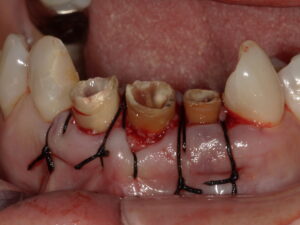

根管治療 の やり直し。

次いで

歯周外科手術。

ファイバーポスト修復。

で

歯型 を 採って

ヤット

完成した オールセラミッククラウン修復を セットした の です。